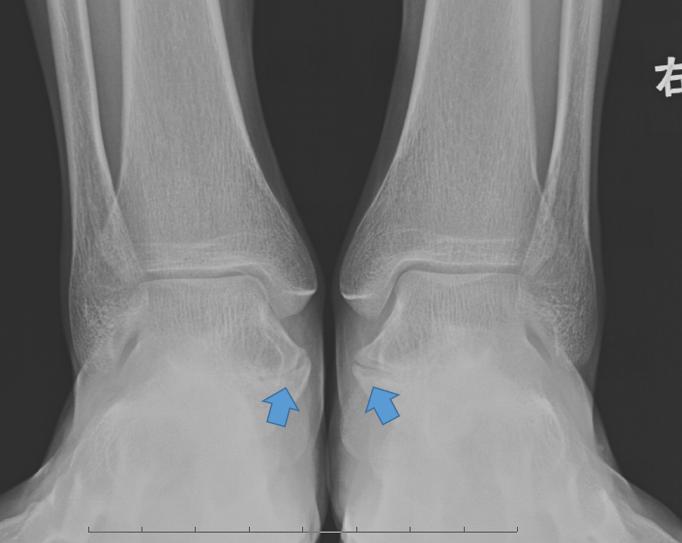

跗骨联合通常指的是跟舟联合(Calcaneonavicular Coalitions)与跟距联合(talocalcaneal coalition)。在临床中有时也习惯称为 骨桥 ,跟距骨桥和跟舟骨桥。跟距联合通常位于内踝下方,也称为内侧跗骨联合(Medial coalition)。

图 | 蓝色箭头指向跟距骨桥

跟距骨桥最早由Zuckerkandl于1877年首次报道。占到跗骨联合中的45%,它的出现是 青少年足部疼痛的一个常见原因 。